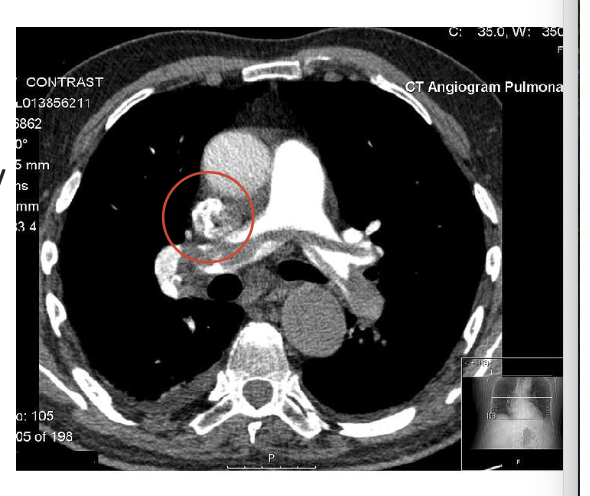

what is depicted in the image?

CT scan showing a pulmonary embolus- spans the R/L pulmonary artery and there is blocked blood flow (gray area within the artery), black areas are the lung fields